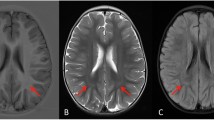

The release of COX6c from mitochondria may be a telling sign of the intrinsic apoptotic pathway, which is consistent with the significant function that COX6c plays in modulating OXPHOS (Fig. 1). Interleukin (IL)-24 controls the production of several genes involved in cell proliferation and death, according to research by Hadife and colleagues [19]. Within the first 6 h, the transcription of genes related to DNA replication and metabolism, such as cell division cycle 6 (CDC6), is inhibited in the B-cell differentiation model. In the later 36 h, IL-24 stimulates COX6c expression and triggers the mitochondrial apoptotic pathway. IL-24-mediated apoptosis in B-cells has been shown to be dependent on p53. Several lines of evidence suggest that p53 can cripple the Warburg effect, where cancer cells exhibit a preferential utilization of glycolysis over aerobic respiration to produce ATP. The related mechanisms involve the regulation of the expression of synthesis of COX (SCO2), a copper-binding protein that is essential for the assembly of COX [20, 21]. Moreover, COX6c expression is remarkably suppressed by glucose, which is also supported by evidence that cells grown in the presence of lactate exhibit approximately 5 times higher COX6c mRNA levels than those grown in glucose [22, 23]. It will be of interest to determine whether COX6c expression is further boosted by p53 under stress conditions, such as glucose deprivation.

COX6c is regulated by multiple factors. (1) On the one hand, APE1 promotes the binding of NRFs to TFAM and regulates mitochondrial biogenesis. In addition, the expression of COX6c is regulated by the redox-dependent coactivator NRFs of APE1; (2) On the other hand, PGC-1α binds to NRFs and ERRα, respectively, to promote the expression of COX6c, which in turn promotes apoptosis and oxidative phosphorylation. During the whole process, COX6c is negatively regulated by miR-4276, Tat, DAZAP1.

Peroxisome proliferator-activated receptor γ (PPARγ) coactivator 1 (PGC-1α), the energetic regulator, is acknowledged as a critical signaling pathway regulating COX6c expression [25]. As a powerful regulator of cellular energy metabolism, PGC-1α is primarily expressed in tissues and organs rich in mitochondria, such as the heart, liver, kidney, brain, brown adipose tissue, and skeletal muscle. PGC-1α initiates the expression of a wide range of coactivated genes involved in virtually all aspects of mitochondrial energy metabolism [26]. NRF-1, one of the most important coactivated targets of PGC-1α, remarkably activates the expression of the gene that encodes COX6c through binding to its promoter [27, 28]. Moreover, NRF-1-binding sites are also identified in the promoter of mitochondrial transcription factor A (TFAM), which subsequently binds to mtDNA and exerts significant effects on mtDNA replication, transcription, and maintenance [26]. The transcriptional activity of both NRF-1 downstream target genes, COX6c and TFAM, is enhanced by an increase in NRF-1 activity upon hydrogen peroxide-induced oxidative stress [29, 30]. The other isoform, NRF-2, plays a parallel role in the transcriptional regulation of COX6c [31, 32]. Furthermore, the human apurinic/apyrimidinic (AP) endonuclease 1 (APE1) has been demonstrated to play an additional regulatory part in the DNA-binding and transcriptional activity of NRF-1 through its redox function, further modulating mitochondrial function after oxidative stress. Knockdown or redox mutation of APE1 impairs NRF-1 DNA-binding activity, consequently reducing the expression of COX6c [29]. Hence, these results suggest that APE1 could be either the redox-dependent coactivator of NRF-1 or the redox-dependent mediator between PGC-1α and NRF-1, which needs to be further clarified. (Fig. 1)

The expression of COX6c is also induced by the estrogen-associated receptor, another PGC-1 partner, and ERRα target genes have a conserved ERR responder (ERRE) in their promoter [33, 34]. In addition, the binding of ERRα to ERRE in its own promoter stimulates its transcription in a positive autoregulatory loop once activated by PGC-1α [26]. COX6c can be used as an endpoint of ERRα activity in contracting cardiomyocytes by measuring changes in the corresponding mRNA level in response to hypoxia. As shown by Cunningham and colleagues [33], contracting adult cardiomyocytes’ adaptive response to persistent hypoxia includes the stimulation of the PGC-1/ERR/COX6c-signaling pathway. Together, the PGC-1α-signaling pathway is essential for the transcriptional regulation of COX6c and further helps maintain mitochondrial function.